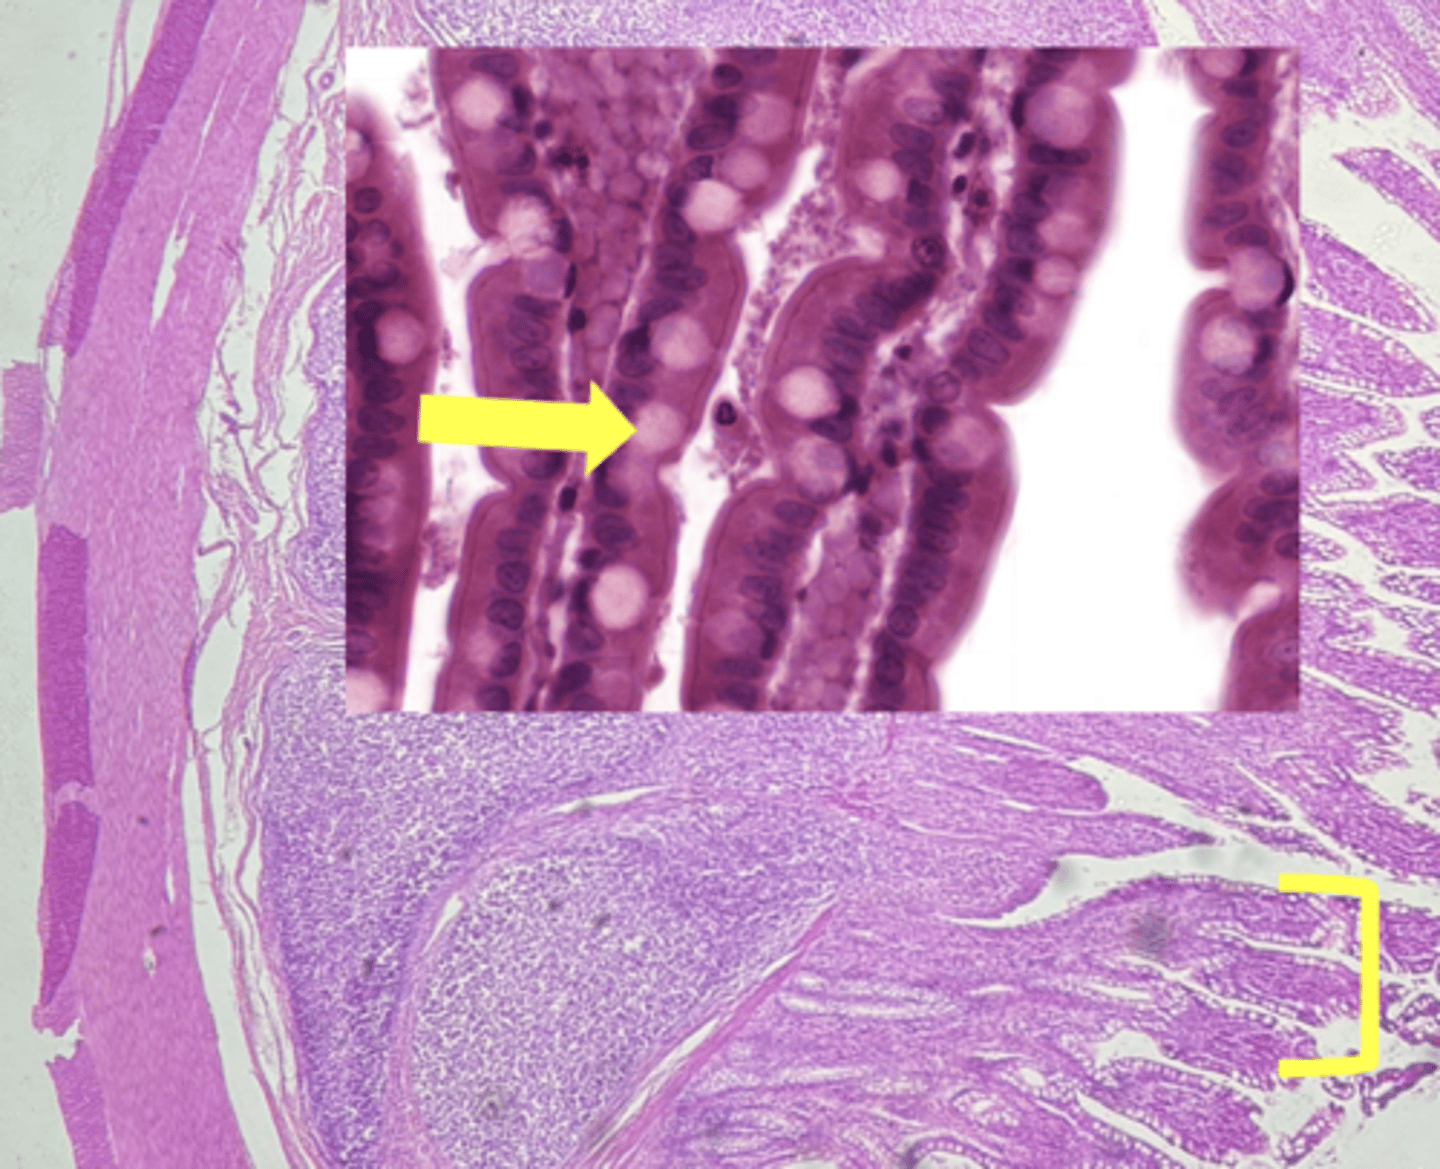

ileum-small intestine

type of tissue

payers patch (KEY CHARACTERISTIC)

(ilium)

villi

(ileum)

simple columnar epithelium

type of cell

goblet cell- mucous (KEY CHARACTERISTIC)

(ileum-increased # seen here)

type of cell & what it secretes

intestinal crypts

lamina propria

muscularis mucosae